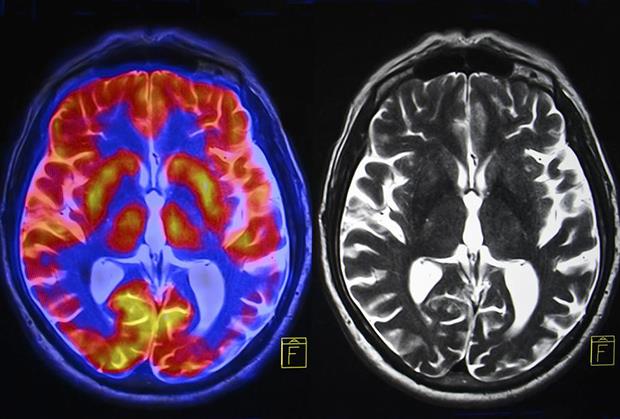

LONDON - Analizom snimaka skenera mozga moguće je otkriti da li neko razmišlja o samoubistvu, što bi moglo da dovede do proboja u lečenju mentalnih bolesti.

Naučnici sa Univerziteta Karnegi Melon u Pitsburgu, Pensilvanija, utvrdili su da ljudi koji razmišljaju o samoubistvu imaju specifičnu moždanu aktivnost, koja se može izmeriti pomoću računara.

To ostavlja mogućnost doktorima da pomognu u lečenju mentalno obolelih i spreče da do suicida dođe. Reči kao što su “smrt” ili “sahrana” kod ovih osoba izazivaju posebne neuronske procese, koji se ne vide kod drugih ljudi.

- Vrlo smo loši u prepoznavanju ljudi koji predstavljaju rizik i koji bi mogli da izvrše samoubistvo. Postoji razlika u načinu na koji suicidalni ljudi razmišljaju o određenim konceptima. Ta razlika se jasno vidi u analizi snimaka na računaru, koji ože da razlikuje ljude koji razmišljaju o samoubistvu od onih koji nisu potencijalne samoubice. Procenat uspešnosti je veći od 90 odsto - kaže Lisa Pan, vođa istraživanja.

Osim toga, program je mogao da razlikuje i ljude koji su pokušali da sebi oduzmu život od onih koji su na to samo pomislili. Studija je obavljena na 34 mladih, što nije veliki uzorak pa će morati da se ponovi na većem broju ispitanika. Naučnici veruju da će moći da dobiju jasnu procenu mentalnog stanja pacijenata.